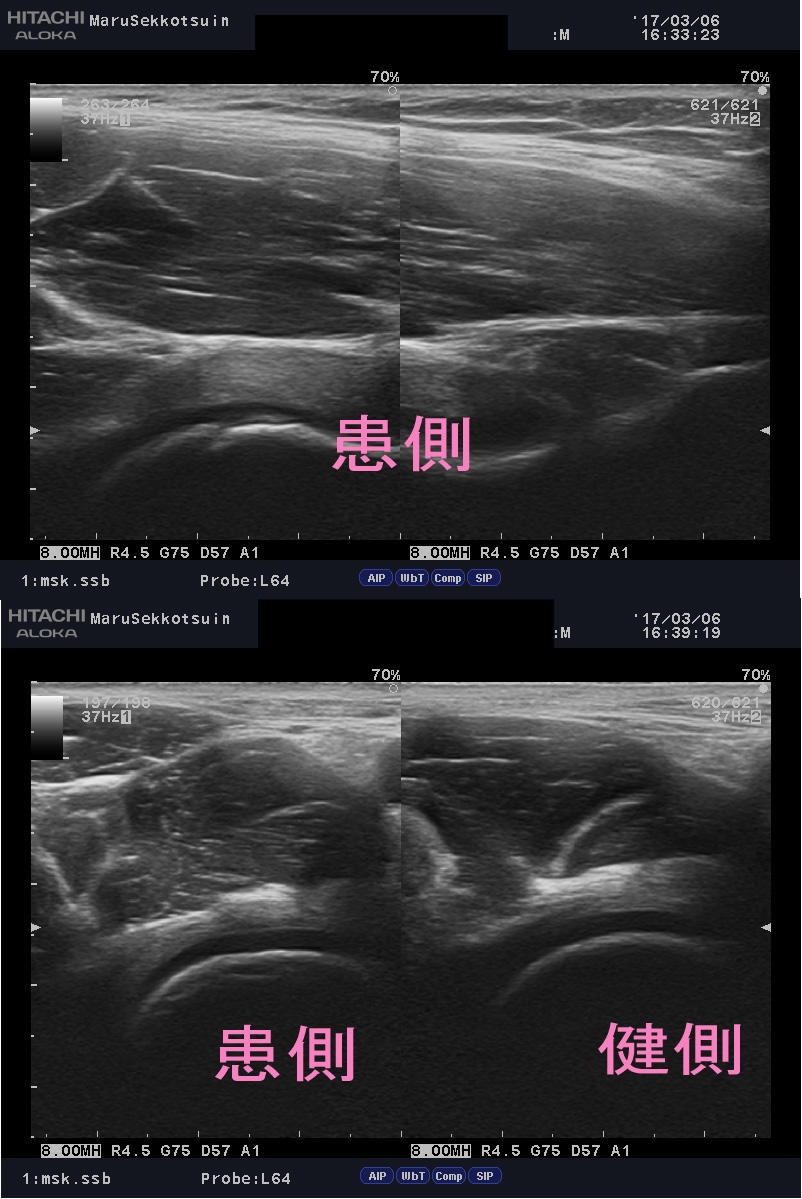

ここ数日の「まる接骨院」流行病。 空手選手の股関節周囲の痛みでございます。 どん...

ここ数日、鼡径部周辺の痛みの症状で ご来院される患者さんが急増中 サッカーなどの...